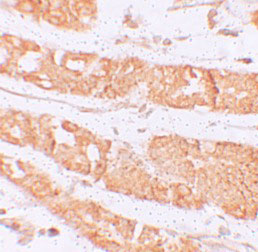

Immunohistochemistry of RHAMM in human stomach tissue with RHAMM antibody at 2.5 μg/mL.